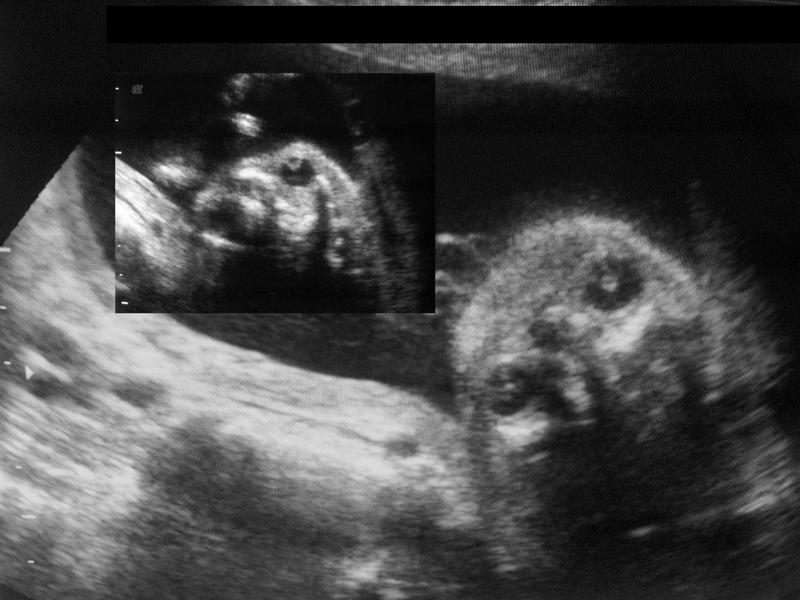

3-D alobar holoprosencephaly

This second trimester fetus shows all the features of alobar holoprosencephaly. The 3-D ultrasound images of the fetal face show absence of the nose or arhinia. In addition, there is a rudimentary single eye seen lower down in the midline. This is known as cyclopia and the fetus is said to be a cyclops. In addition, the 2-D ultrasound image of the fetal brain shows a single common ventricle or what is known as a mono-ventricle running from one side to the other with absence of midline structures such as the falx cerebri. Besides, both the thalami appear to be fused forming a single structure. Also, surrounding the mono ventricle is a rim of cerebral cortical tissue. All these ultrasound features are suggestive of a severe case of holoprosencephaly also known as alobar holoprosencephaly. The above ultrasound images of alobar holoprosencephaly are courtesy of Dr. Rami Barakat, MD.